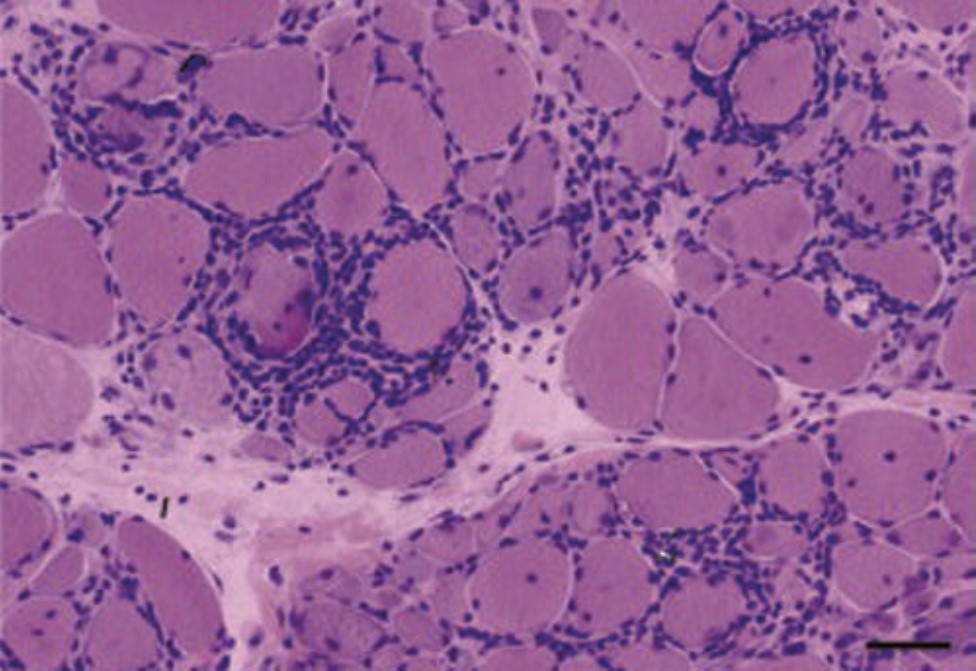

Question: A 40-year-old woman underwent muscle biopsy for progressive weakness, among other symptoms. Which of the following is her most likely diagnosis based on the image shown?

Correct Answer: Polymyositis

Explaination: The image demonstrates endomysial lymphocyte infiltration indicative of polymyositis. This pattern is in contrast to dermatomyositis, where biopsy shows perifascicular inflammatory infiltrate only. Emery Dreifuss muscular dystrophy is an X-linked disease that tends to affect boys between the ages of 5 and 15, with no inflammatory pathological findings, but with dystrophic features, including wide variation in fiber size and increased fibrous and adipose tissues. Inclusion body myositis is an inflammatory myopathy, with pathology showing vacuoles with basophilic granules